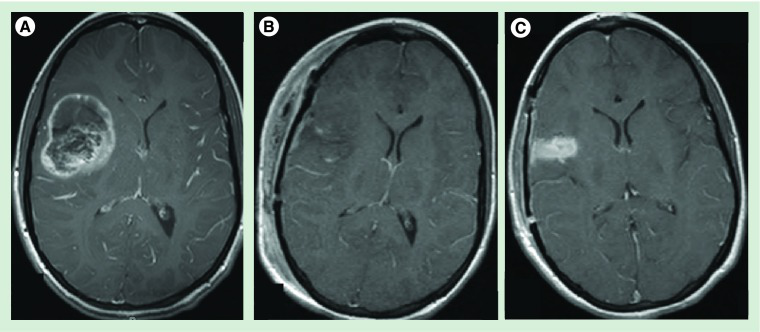

儿童颅内室管膜瘤的治疗从较顺利的手术切除开始。大多数系列在GTR治疗二级和三级颅内室管膜瘤后显示出好转的结果。切除的范围应通过与神经外科医生讨论和术后立即成像来确定。脑部磁共振成像应在手术后48小时内进行,这是在术后效果开始用钆增强之前。这一时间窗后的术后成像将使区分术后变化和残余增强肿瘤几乎不可能。核磁共振成像观察到的典型术前和术后变化如图所示图3。在较大限度的顺利切除后,需仔细评估患者的播散性疾病,因为二级和三级肿瘤都有很小但公认的扩散到整个颅脊髓轴的趋势。诊断时已公布的播散性疾病发生率在0到21%之间,并且似乎与肿瘤的级别和位置无关。播散性疾病的存在较大地影响了放射治疗的。因此,在诊断时确定疾病的程度至关重要。虽然切除部位的术后成像应在48小时内进行,但脊柱的成像应在术前进行,或在切除后延迟约10-14天进行,以避免术后即刻的碎片和血液制品被误解为点滴转移。除非脊柱磁共振成像显示明确的液滴转移,否则应对全部患者进行腰椎穿刺脑脊液细胞学检查,以排除显微镜下的扩散。理想情况下,这应该在脊柱磁共振成像后进行,至少在切除后10-14天进行。播散性疾病的存在不仅影响预后,也影响后续的治疗建议。患有局限性疾病的患者是切除腔辅助局灶性放射治疗的候选对象,而患有播散性疾病的患者,无论是在磁共振成像上观察到的粗大播散还是细胞学阳性,或者两者兼有,都需要进行颅脊髓放射治疗。